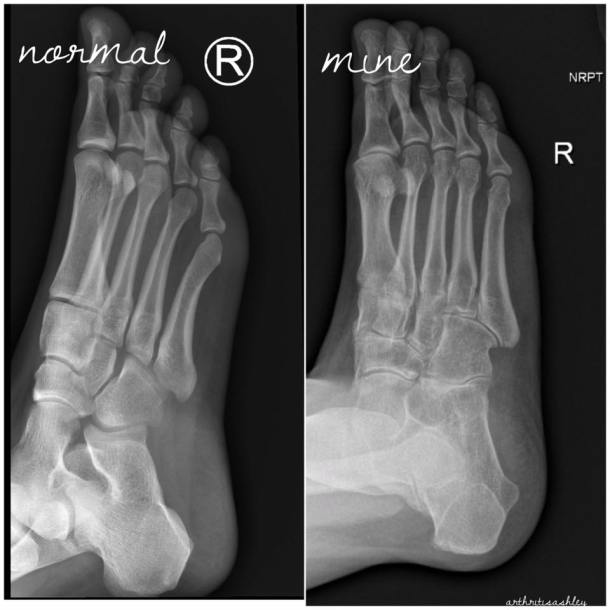

I thought I’d share these as a follow-up to my “My Joints are 90 Years Old” post.

My left wrist and right foot are beyond surgical repair.

I’ve been told that my joints look 80 or 90 years old!

How can you tell? Compare joint space, shape, white areas. JIA, RA, and OA have ravaged the joints.